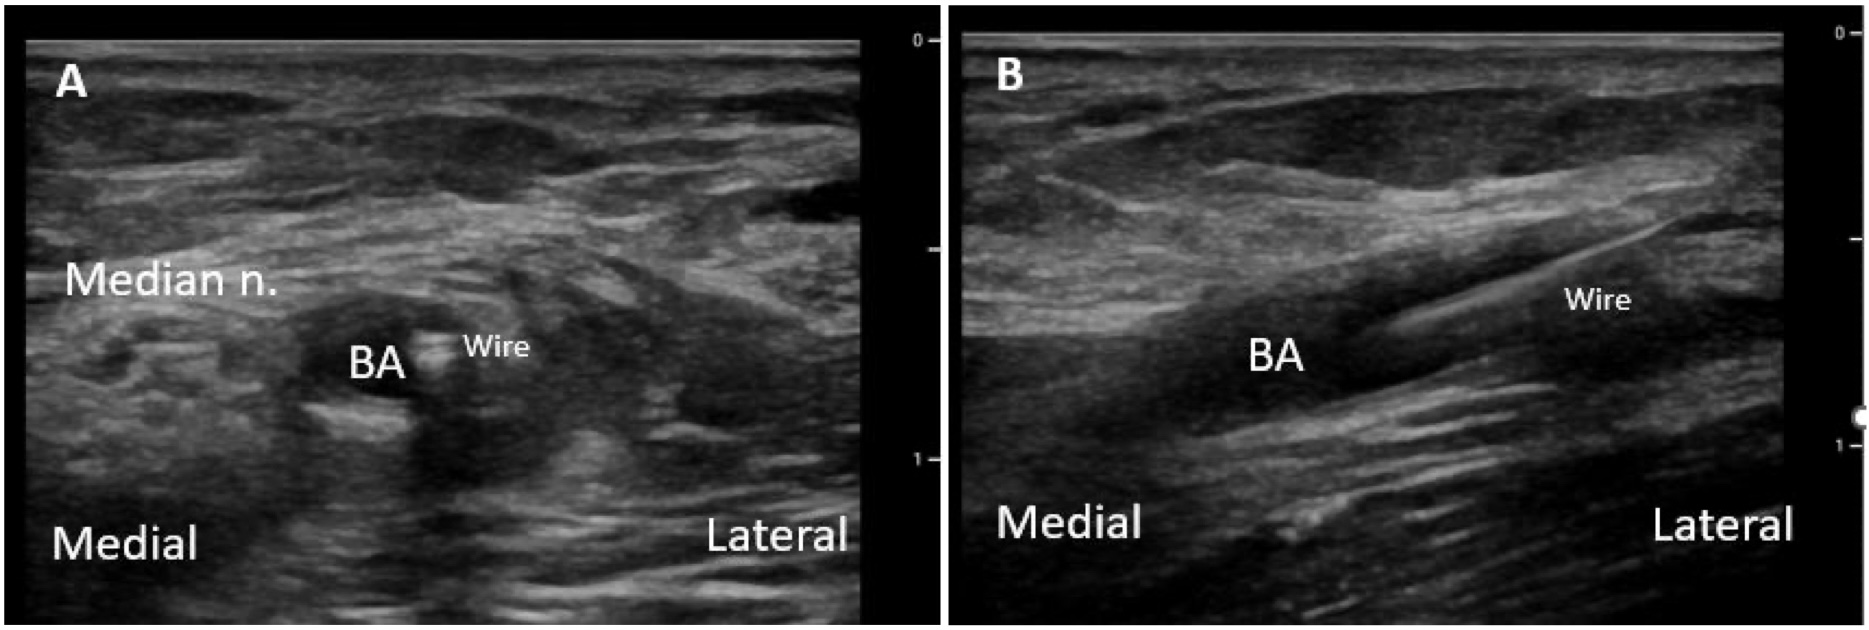

The brachial artery (BA) is found on the medial side of the antecubital fossa between the biceps brachii muscle and the pronator teres muscle. Of important note, the median nerve lies just medial to the artery at this location and is at risk of injury during attempts at arterial access (Video 9).

Center the target artery in the middle of the ultrasound screen and enter the skin proximal to the probe at a 45-degree angle (Figure 3). A shallower insertion angle will likely be necessary if the RA is superficial. Fujii and Jones (2017) describe the technique of tilting the transducer away from the operator until the needle tip disappears from the screen and then slowly advancing the needle until the tip reappears slightly deeper, repeating this maneuver until a slight “pop” is felt. The needle tip enters the artery.7 This will appear as a “bullseye.”

It is important to focus on the ultrasound screen rather than on the catheter, and it may be helpful to have another person watching for the “flash” of blood once the artery is entered. If the artery is entered off-center, this may result in an inability to thread the catheter. If multiple prior attempts have been made, it is best to move more proximally to avoid any hematoma from forming. Other potential complications include thrombosis, arterial dissection, pseudoaneurysm formation, nerve damage, or infection. If the patient already has a compromised collateral ulnar arterial flow, hand ischemia can result from injury or occlusion of the RA. Injury or occlusion of the BA can result in limb ischemia. In addition, the median nerve is near the BA, and transection can result in permanent nerve injury.